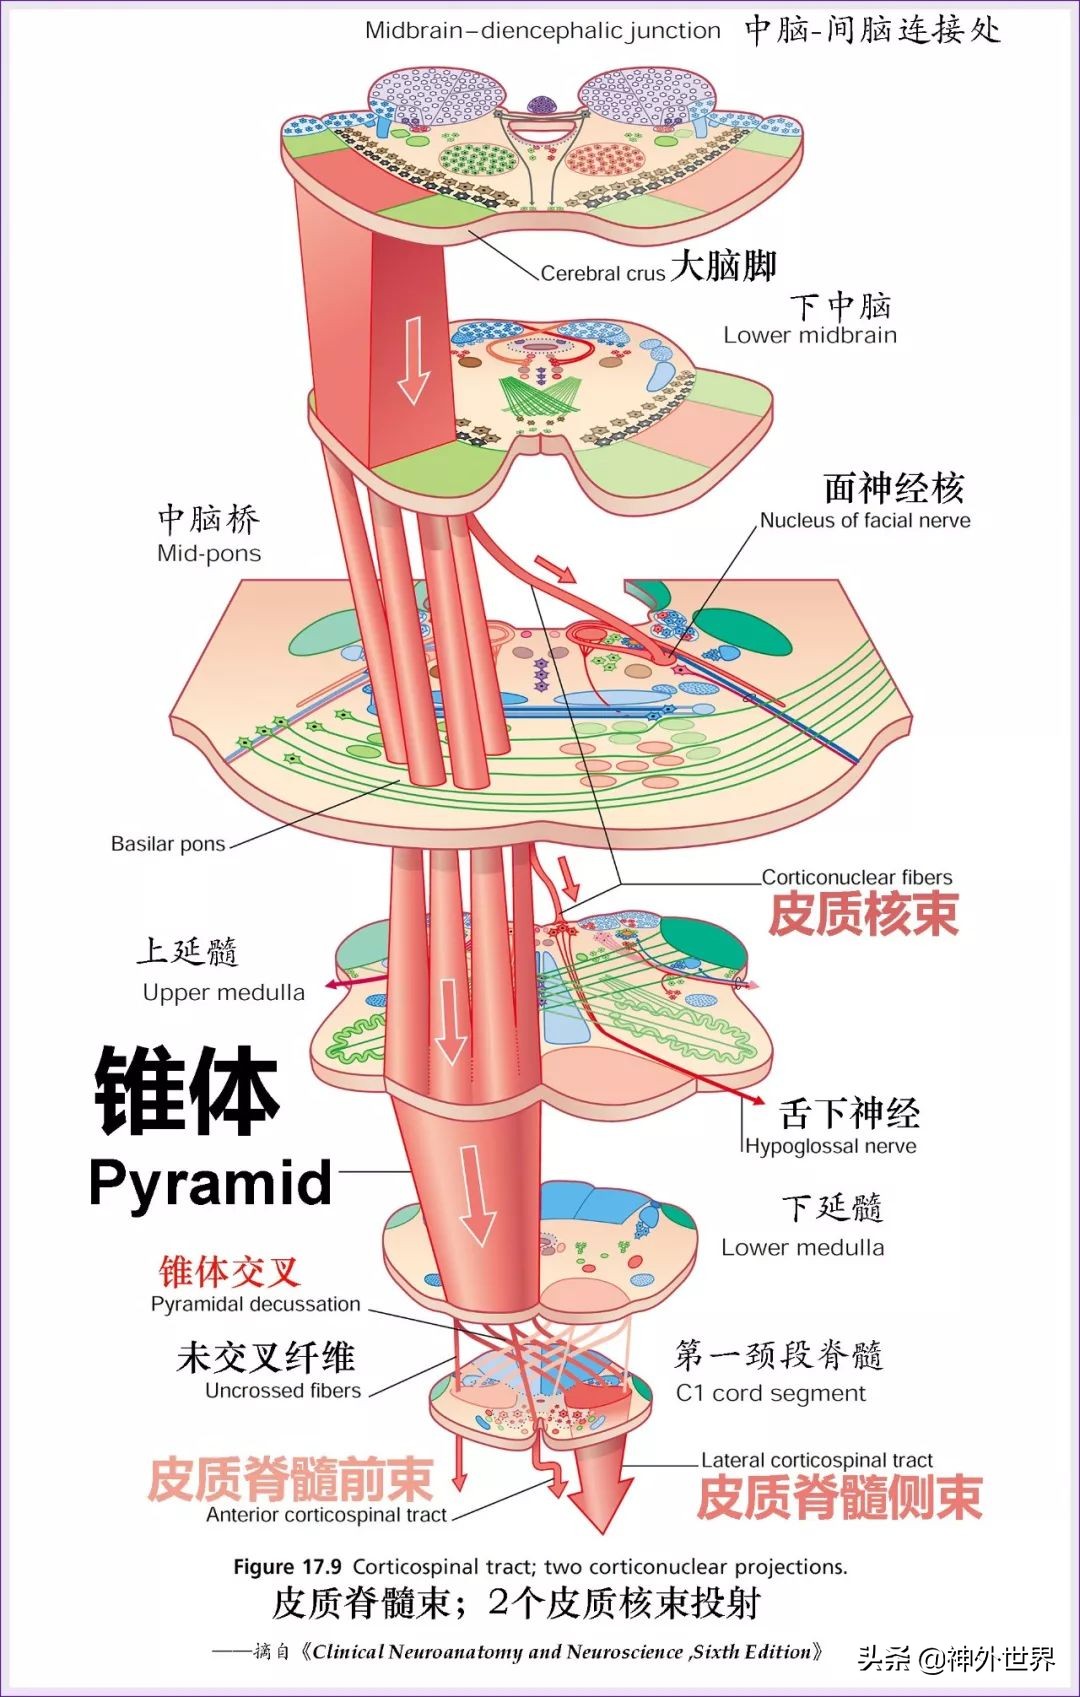

- 传导束:①最大的下行传导束——锥体束,位于基底(脑干腹侧)。②上行的感觉通路——4个丘系(内、外、脊髓、三叉),位于背侧(脑干被盖)。③脑干内协调眼球运动及头晕协调运动的传导束——内侧纵束。④协调交感副交感活动的传导束——背侧纵束。⑤大脑与小脑沟通的传导束——下行(皮质-脑桥-小脑束、皮质-橄榄-小脑束等);上行(小脑上脚内的齿状核-红核-纹状体通路)。⑥脑干发自脑干的4条下行通路(顶盖-脊髓束;红核-脊髓束;网状-脊髓束;前庭-脊髓束)→都是协调运动,使运动更精准的。